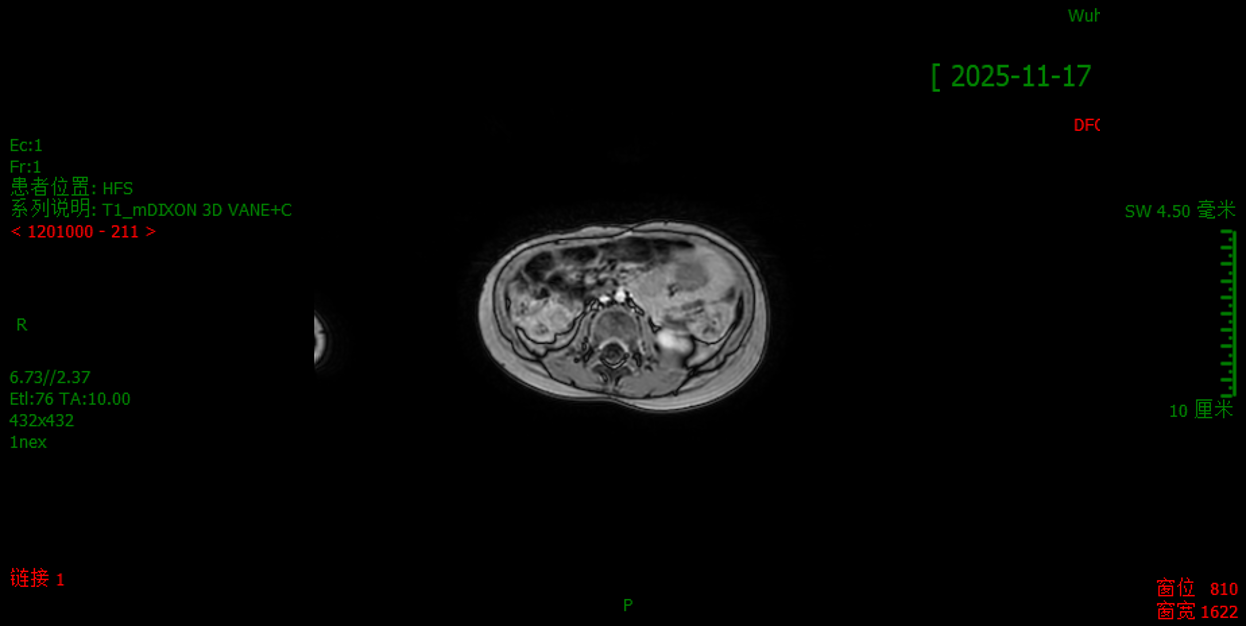

2025.11.17

NSE、LDH、BNP均正常。颅脑+腹部MRI:右侧肾上腺区肿物切除术后,增强未见明显异常强化影或弥散受限;腹盆腔未见明显肿大淋巴结影;颅脑未见明显异常。疗效评价:CR。